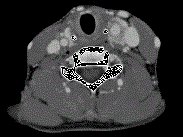

问题 女,39岁,左颈部可扪及一肿块,无发热,无疼痛,CT如图所示,最可能的诊断是 ( )

选项 A、颈部海绵状血管瘤 B、颈动脉瘤 C、颈动脉体瘤 D、颈部神经纤维瘤 E、颈部神经鞘瘤

答案 C